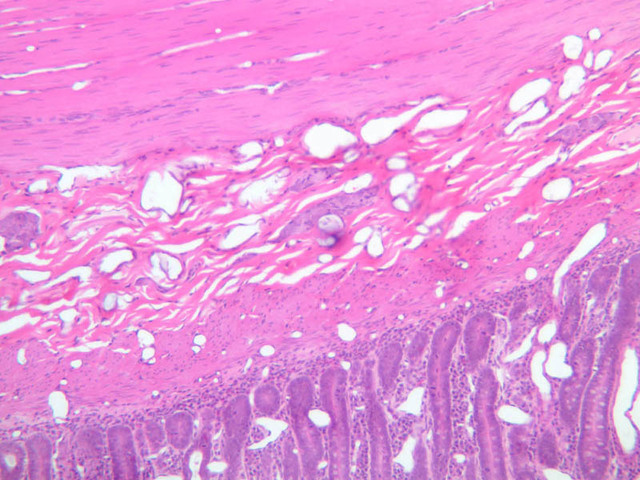

Examine a section through the pyloroduodenal junction (slide B-10, H&E [2.5x-labeled, 10x, 20x, 40x]). Compare the mucosal glands in the pylorus with those in the duodenum and note the relationship of the muscularis mucosae to the submucosal glands (Brunner's glands) of the duodenum (B-10, H&E [2.5x-labeled] [2.5x, 10x] [2.5x, 10x, 20x, 40x]). The thickened musculature of the pyloric sphincter should be apparent in this section. This region of transition may also show exceptionally large amounts of lymphoid tissue in the mucosa (B-10, H&E [2.5x, 10x, 20x, 40x]. In some of your sections goblet cells appear blue due to overstaining.